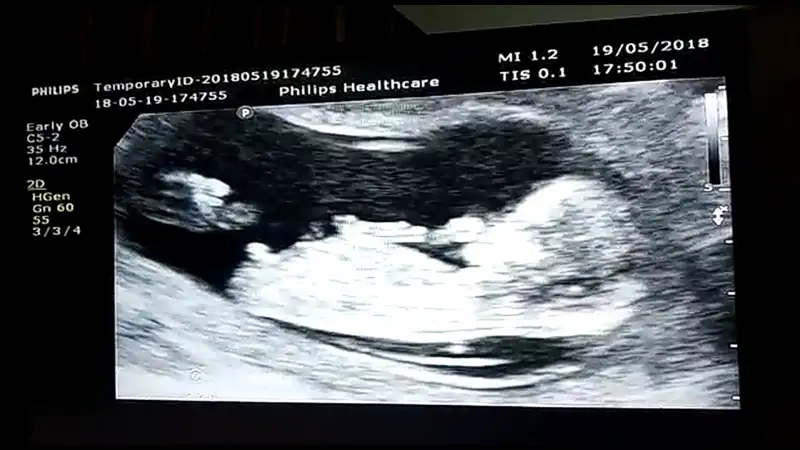

Kuzum,erkegin nubu cok dik gidiyor kızın ise paralel.benim kızımın bariz paraleldi belliydi.iste tahmin etmek te guzel :))

kuzular nubu görünen bi ultrason fotosu yok mu?eger nub net belliyse ben anlarim kiz mi erkek mi :KK45:

Tahmin et bakalım teyzesi :)

Amin Allah razı olsun canım sağlıklı ve hayırlı evlat olsunlar da gerisi teferruat :) başta kız olsun diye hevesliydim ama doktor erkeğe benziyor dedikten sonra adını bile koyduk Yusuf beyin :) şimdi abisiyle boğuşacakları günlerin hayalini kuruyorum :)